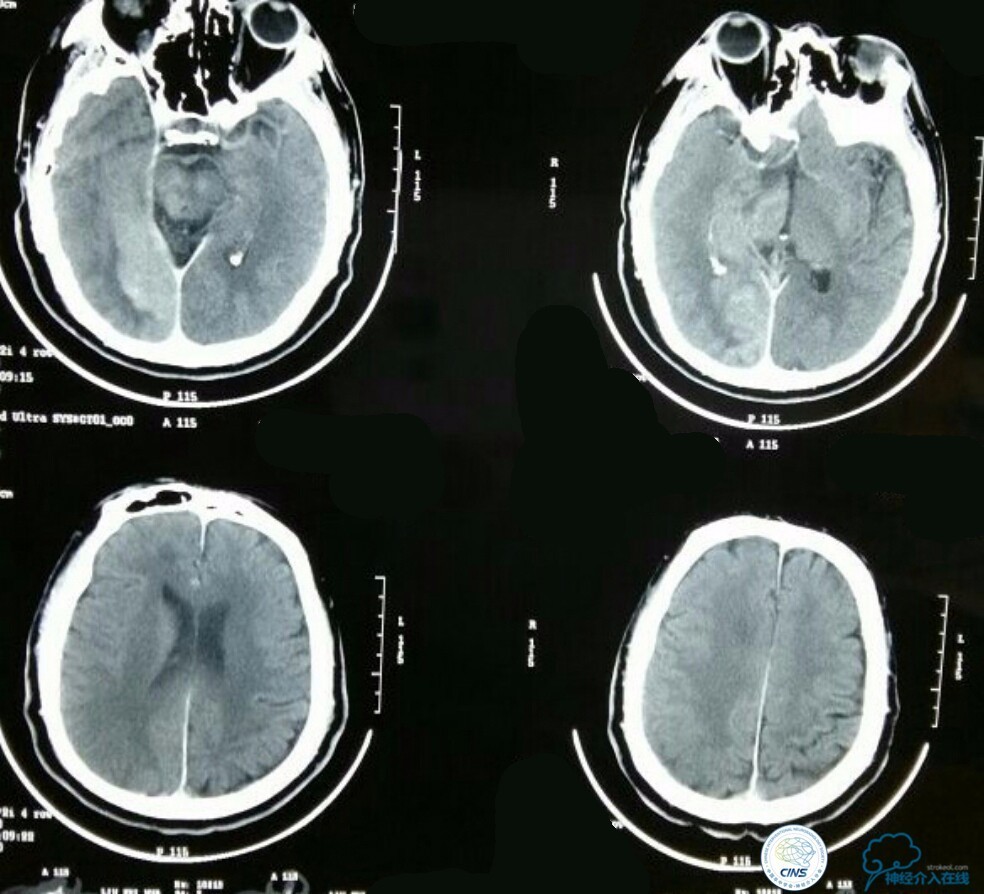

术后生命体征平稳,成功撤呼吸机,肌力较前好转,复查头颅CT:

右侧丘脑高密度影,右侧枕叶可能也有梗死,祈祷慢慢恢复吧!